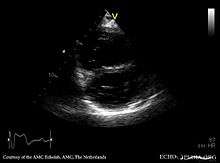

The diagnosis of pulmonary valve stenosis can be achieved via echocardiogram, as well as a variety of other means among them are: ultrasound, in which images of the heart chambers in utero where the tricuspid valve has thickening (or due to Fallot's tetralogy, Noonan's syndrome, and other congenital defects) and in infancy auscultation of the heart can reveal identification of a murmur.[8]

- Echocardiographic assessment of Pulmonary valve stenosis from WikiEcho